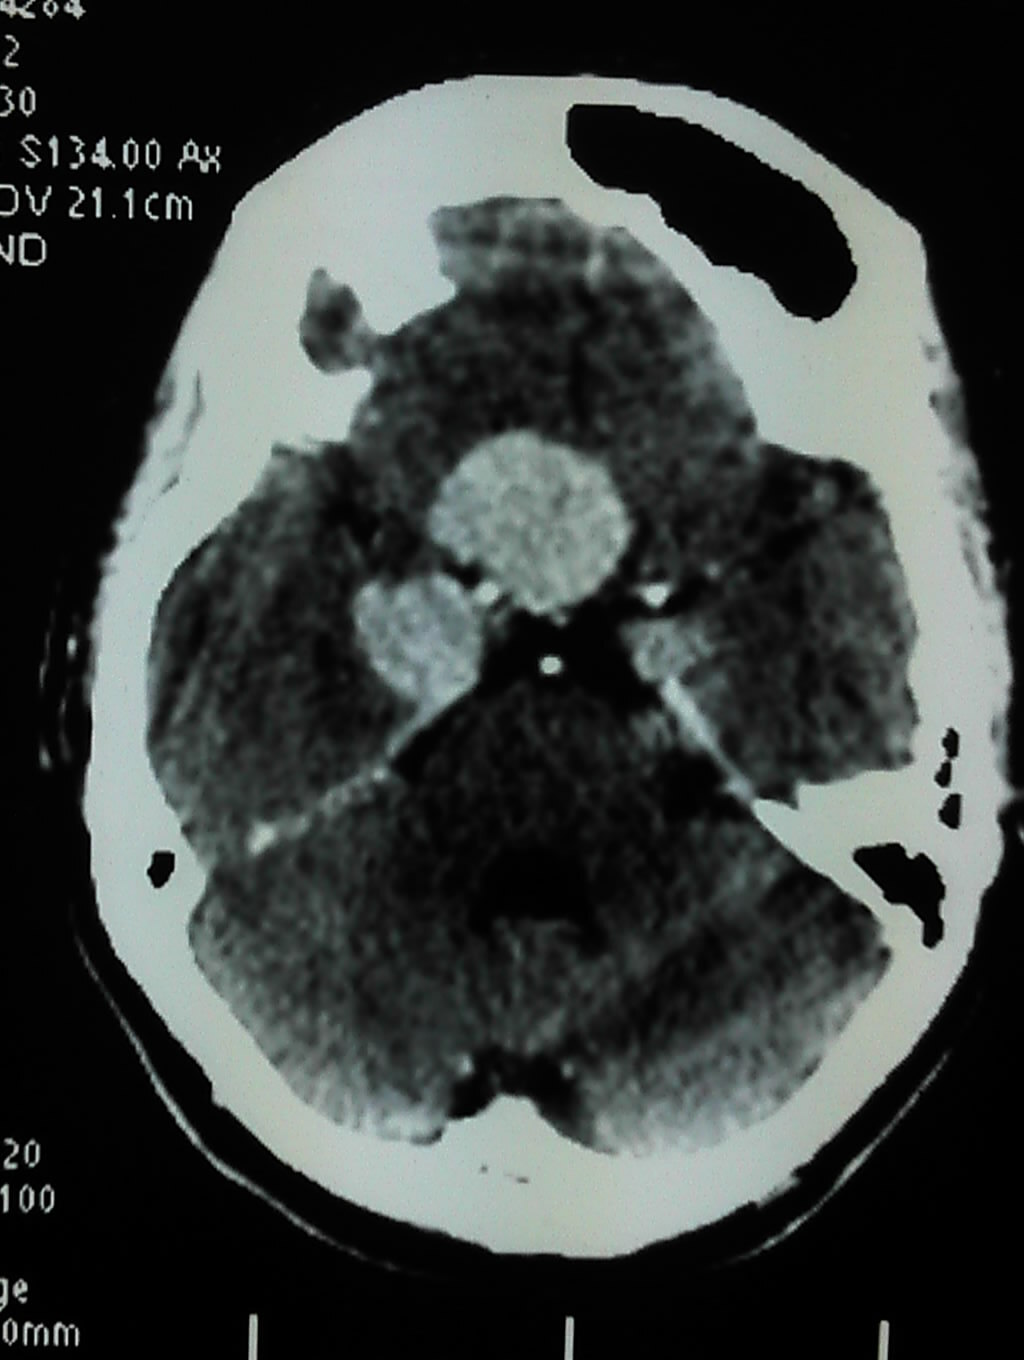

下面是病人的最早的影像资料: